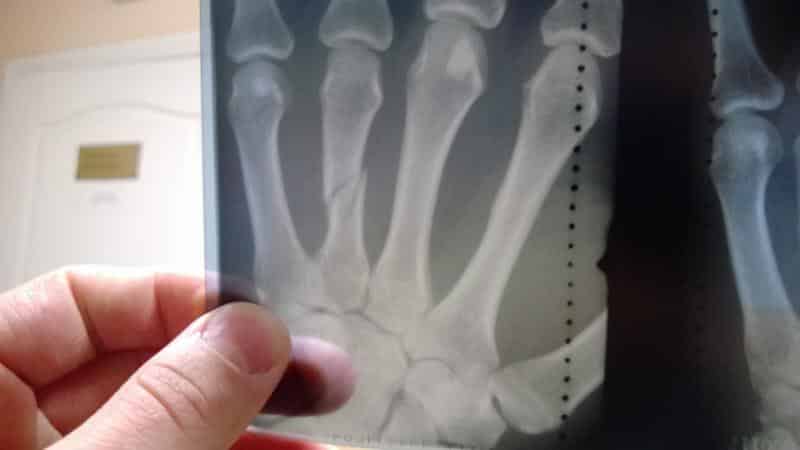

На начальном этапе артроза дискомфорт незначителен. Боли в пальцах могут возникать время от времени, быть слабо выраженными и чередоваться с периодами, когда симптомы практически отсутствуют. Сужение суставной щели на этом этапе можно заметить только на рентгеновском снимке.

Вторая стадия заболевания сопровождается постоянными болями. На этом этапе уже можно визуально заметить отечность пальцев и начальные признаки деформации. Поскольку сужение суставной щели продолжается, фаланги начинают соприкасаться друг с другом.

Это негативно сказывается на подвижности стопы. При сгибании пальцев рук суставы могут издавать хруст, также наблюдается отечность. Рентгеновский снимок в этом случае покажет значительное количество остеофитов.

Для подтверждения диагноза и выявления болезни на более ранних стадиях используется рентгенография. Этот метод позволяет обнаружить начальные признаки разрушения хрящевой ткани.